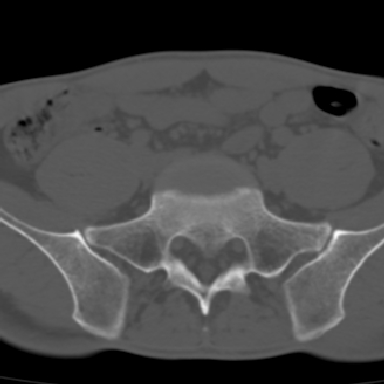

m 30 腰背部不适半年; 清晨时僵硬; 活动症状有所改善

双侧骶髂关节下2/3关节面模糊,毛糙,可见小囊状骨质破坏区.支持强直性脊柱炎.

强直性脊柱炎的早期改变!不仅表现为双侧骶髂关节,第5腰椎与骶椎间的关节突关节也有类似改变。

双侧骶髂关节下2/3关节面模糊,毛糙,髂骨侧可见小囊状骨质破坏区,骶髂关节间隙增宽(软骨破坏期)。支持早期强直性脊柱炎。

双侧骶髂关节下2/3关节面模糊、毛糙,可见小囊状骨质破坏区,呈虫咬状改变,周围可见增生硬化.支持强直性脊柱炎早期表现.

双侧骶髂关节髂骨面硬化,毛糙,小囊变,属于早期强直性脊柱炎